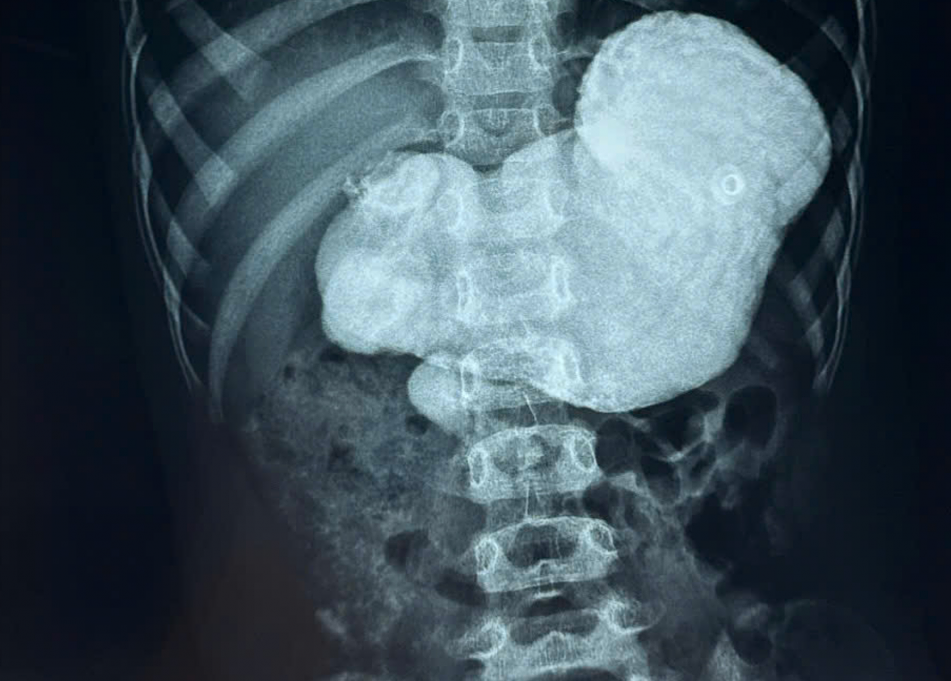

BS Nguyễn Hiền - Khoa Ngoại tổng hợp - cho biết trong quá trình mổ, bác sĩ phát hiện toàn bộ ruột non của bé bị xoắn 720 độ, khiến hệ thống mạch máu nuôi ruột bị đình trệ, đe dọa hoại tử. Bằng thiết bị nội soi chuyên dụng, các bác sĩ tháo xoắn ruột kịp thời, khôi phục tuần hoàn máu và cố định ruột để ngăn ngừa tái phát.